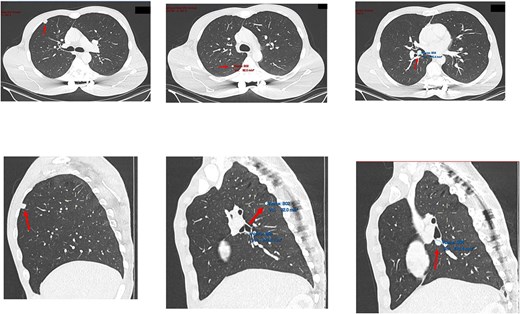

Four days after the surgery, the patient was re-admitted due to fever, cough, and some small-volume purulent discharge from his drain site. A repeat chest radiograph (Fig. 4) was unremarkable, and a wound swab was negative. He was empirically treated with 24 hours of intravenous antibiotics and given a short 4-day course to complete at home. It was felt by the team that a lower threshold for treatment of infection would be appropriate, given his diagnosis of CIP. He was discharged 1 day after re-admission and made a good recovery.

Repeat chest radiograph on re-admission to hospital with fevers and tachycardia.